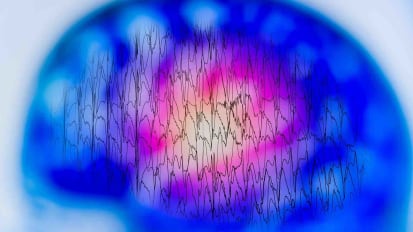

New Tools Map Seizures, Improve Epilepsy Treatment

Two new models could solve a problem that’s long frustrated millions of people with epilepsy and the doctors who treat them: how to find precisely where seizures originate to treat exactly that part of the brain.

Identifying the Seizure Onset Zone Through Single-Pulse Electrical Stimulation

New study by Johns Hopkins researchers could significantly shorten monitoring time before epilepsy surgery and improve outcomes